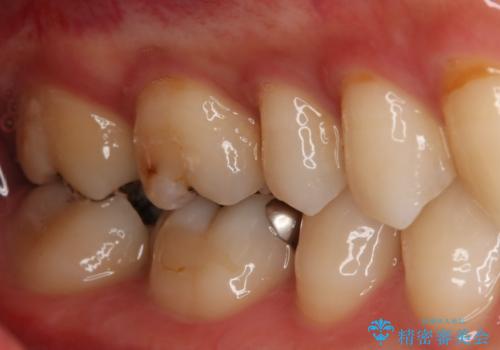

- 右上下6番の銀歯のやり変えを希望された患者様です。

切削量・形態を考慮し、上はセラミッククラウン、下はセラミックインレーでの治療を選択しました。

上はう蝕が歯頚部まで達していたのでクラウンでの治療を選択しました。

銀歯直下もう蝕が進行していたので全て除去した上でCRにて裏層しています。

下はクラウンほど切削量が多くないと判断し、インレーでの治療を選択しました。